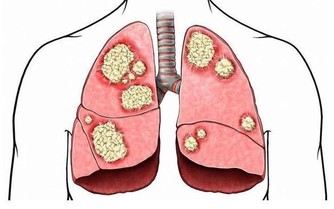

7、肝腹水:

肝腹水一般在肝病晚期或病情極為嚴重時才會出現,如肝硬化出現肝腹水表示已經進入肝硬化晚期。